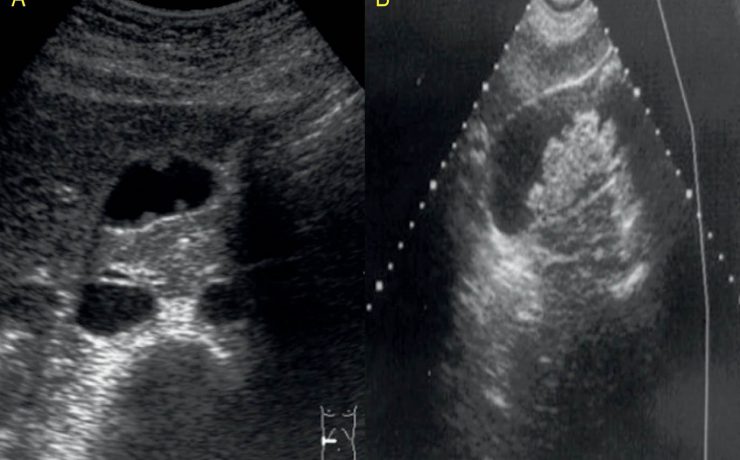

Rotura uterina por acretismo placentario

La rotura uterina durante el embarazo es una de las complicaciones más graves, que aumenta la morbilidad y mortalidad materna y fetal. La rotura uterina por placenta percreta es rara. La rotura uterina es cualquier desgarro, fracción o solución de continuidad supracervical en el útero que sucede durante el embarazo,